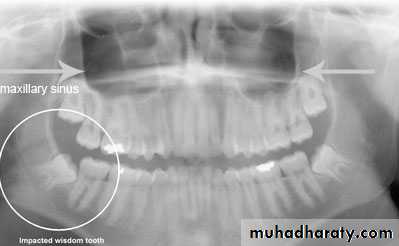

Classification of impacted upper third molar1- pell and Gregory according to the relation of the impacted tooth to the occlusal plane of the upper second molar

2- the relation of the impacted upper third molar to the maxillary sinus

Relation of the impacted maxillary third molar to the maxillary sinus

Class A sinus approximation ( less than 2 mm bone between the antrum and the impacted tooth )Class B non sinus approximation ( more than 2 mm of bone exist between the impacted tooth and the sinus )